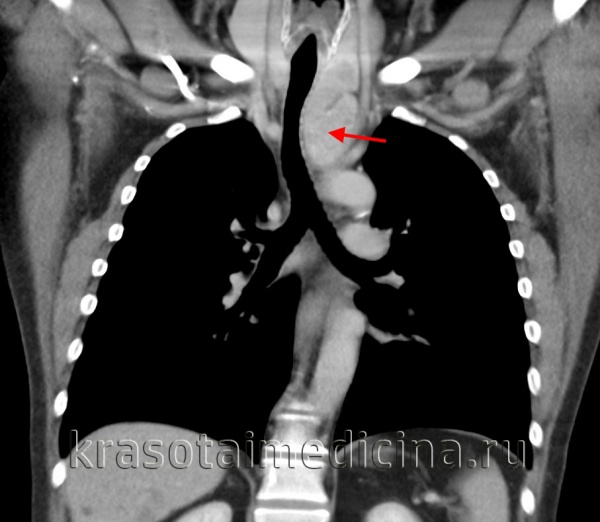

Расширение тени средостения на обзорном снимке влево в области аорто-пульмонального окна, в области талии сердца и при томографическом исследовании прекрасно виден конгламерат увеличенных лимфатических узлов, которые располагаются в переднем средостении. Объемные образования, которые состоят из множества лимфатических узлов, отличают такой процесс от обычных опухолей средостений.

С другой стороны, эти лимфатические узлы могут вырастать в патологическое образование, которое совершенно неотличимо ни от каких других опухолей средостений, с признаками инвазии, с вовлечением в грудной стенке, со сдавлением крупных сосудов, со стеснением и сужением трахеи главных бронхов.

Другой пример. Болезнь Кастельмана. Здесь специально оставлены денситометрические показатели. Средняя плотность образования, которое располагается между типичных образований, между восходящей и нисходящей аортой и оттесняет трахею сзади и справа, составляет почти 140 или 150 единиц (неразборчиво, 15:07).

Практически так же как контрастированная кровь. Очень немногие патологические образования средостения реагируют таким образом на введение контрастного вещества. В этом случае сочетание точной локализации и реакции на контрастный препарат позволяют предположить правильный диагноз.